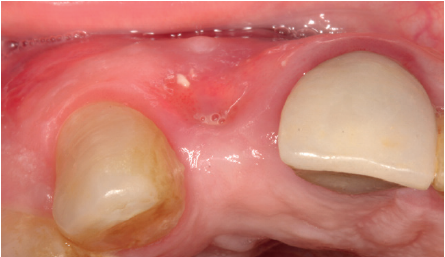

Para continuar con el estudio del caso se realiza un Cone-Beam donde poder observar tridimensional ente la posición del implante situado en posición 1.2. En los cortes seccionales se visualiza completamente situado hacia vestibular con una reabsorción casi completa de la cortical ósea de esta área, lo que explica los problemas de tejido blando subyacente. En la radiografía periapical se observa la posición del implante con respecto a los dientes adyacentes

(Figuras 5 y 6). Con esta imagen se procede a la apertura de un colgajo y la explantación del implante. Se retira también la corona situada en el diente 1.1 para poder realizar otra corona que servirá para apoyar el provisional en extensión para la zona del 1.2, mientras cicatriza la primera intervención. En este primer abordaje se coloca también un injerto en bloque obtenido de la rama mandibular que se fija con un microtornillo en la zona a regenerar donde se ha perdido la cortical vestibular. Una vez fijado y posicionado, se rellena alrededor del injerto en bloque con hueso particulado obtenido con un bone-scraper de la misma zona donante embebido en PRGF-Endoret para una mejor fijación y viabilidad celular (Figuras 7-9).